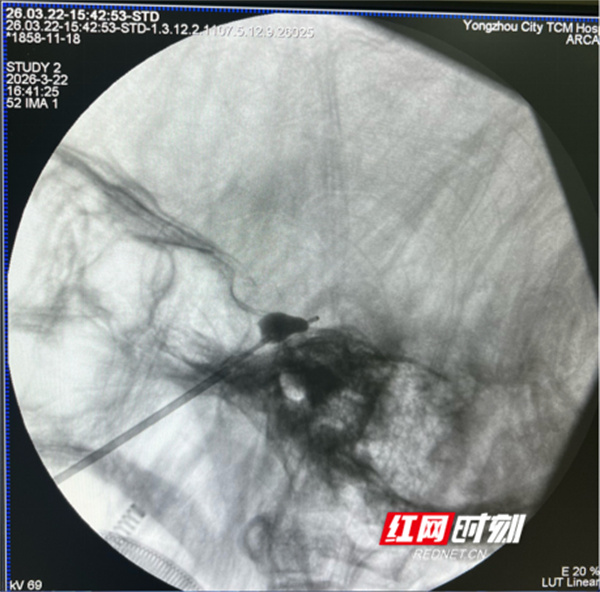

考虑到谭奶奶年事已高、合并多种基础疾病,脑病科医疗团队联合麻醉科团队开展多学科联合会诊,综合评估其身体状况与病情后,决定采用C臂辅助下经皮穿刺三叉神经球囊压迫术这一微创方案。

该手术无需开颅,仅用一根细穿刺针,从口角旁穿刺至颅底,将微小球囊置入特定部位,阻断痛觉神经传导即可,全程仅耗时30分钟。手术创伤极小,只留下一个针眼,无需缝合。术后,谭奶奶的疼痛立刻缓解,困扰她两年多的病痛终于消失。